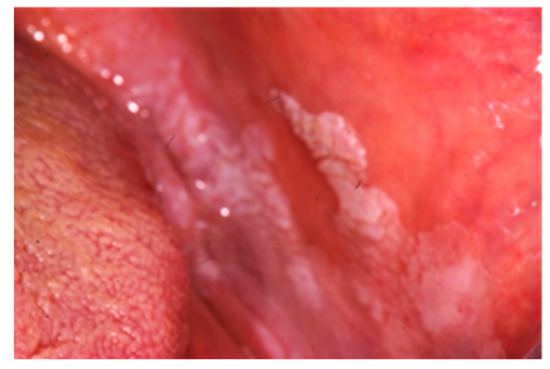

| Cobblestoning the mucosa | X | ||

| Granulomatous cheilitis | X | ||

| Mucosal tags | X | ||

| Pyostomatitis vegetans | X | ||

| Unspecific manifestations | Deep oral fissuring | X | |

| Cheilitis angularis | X | X | |

| Dental caries | X | X | |

| Mucogingivitis | X | X | |

| Periodontitis | X | X | |

| Lichen planus | X | X | |

| Dysphagia | X | X | |

| Dry mouth | X | X | |

| Halitosis | X | X | |

| Taste changes | X | X | |

| Aphthous ulcerations | X | X |